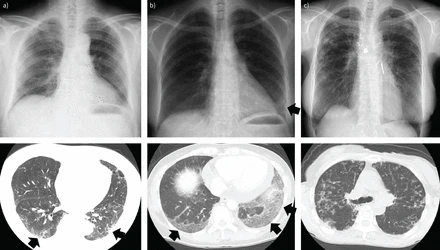

Однією з найбільших проблем у веденні пацієнтів з ILD є диференціація. Лікарям потрібно чітко розрізняти запальний та фібротичний компоненти. Існуючі методи візуалізації мають обмеження в цьому плані. Комп’ютерна томографія високої роздільної здатності є золотим стандартом. Вона дозволяє оцінити структурні зміни легеневої тканини. Однак вона не завжди може відрізнити активне запалення від фіброзу. Це призводить до суб’єктивності в інтерпретації. Біопсія легень є інвазивною процедурою з ризиками ускладнень. Вона не підходить для динамічного спостереження.

Візуалізаційні методи відіграють центральну роль у діагностиці ILD. Вони допомагають встановити діагноз та оцінити тяжкість. Також вони дозволяють виключити інші патології. КТ органів грудної клітки є основним методом. Вона дає детальну картину структурних змін. Однак функціональні методи мають додаткові переваги. Позитрон-емісійна томографія з фтордезоксиглюкозою використовується обмежено. Вона має обмежену специфічність до запалення в легенях. Новаційні радіофармпрепарати можуть заповнити цю прогалину.

Попередні дані фази 2 клінічного дослідження PREDICT-ILD. Попередні дані другої фази виглядають обнадійливо. Вони показали можливість візуалізації запалення у пацієнтів з фіброзною ILD. Повні результати дослідження очікуються протягом цього року. Дослідження PREDICT-ILD має проспективний дизайн. Воно включає кількісну оцінку КТ-зображень. Метою є оцінка прогресування інтерстиційної хвороби легень. Також досліджується кореляція з клінічними параметрами.